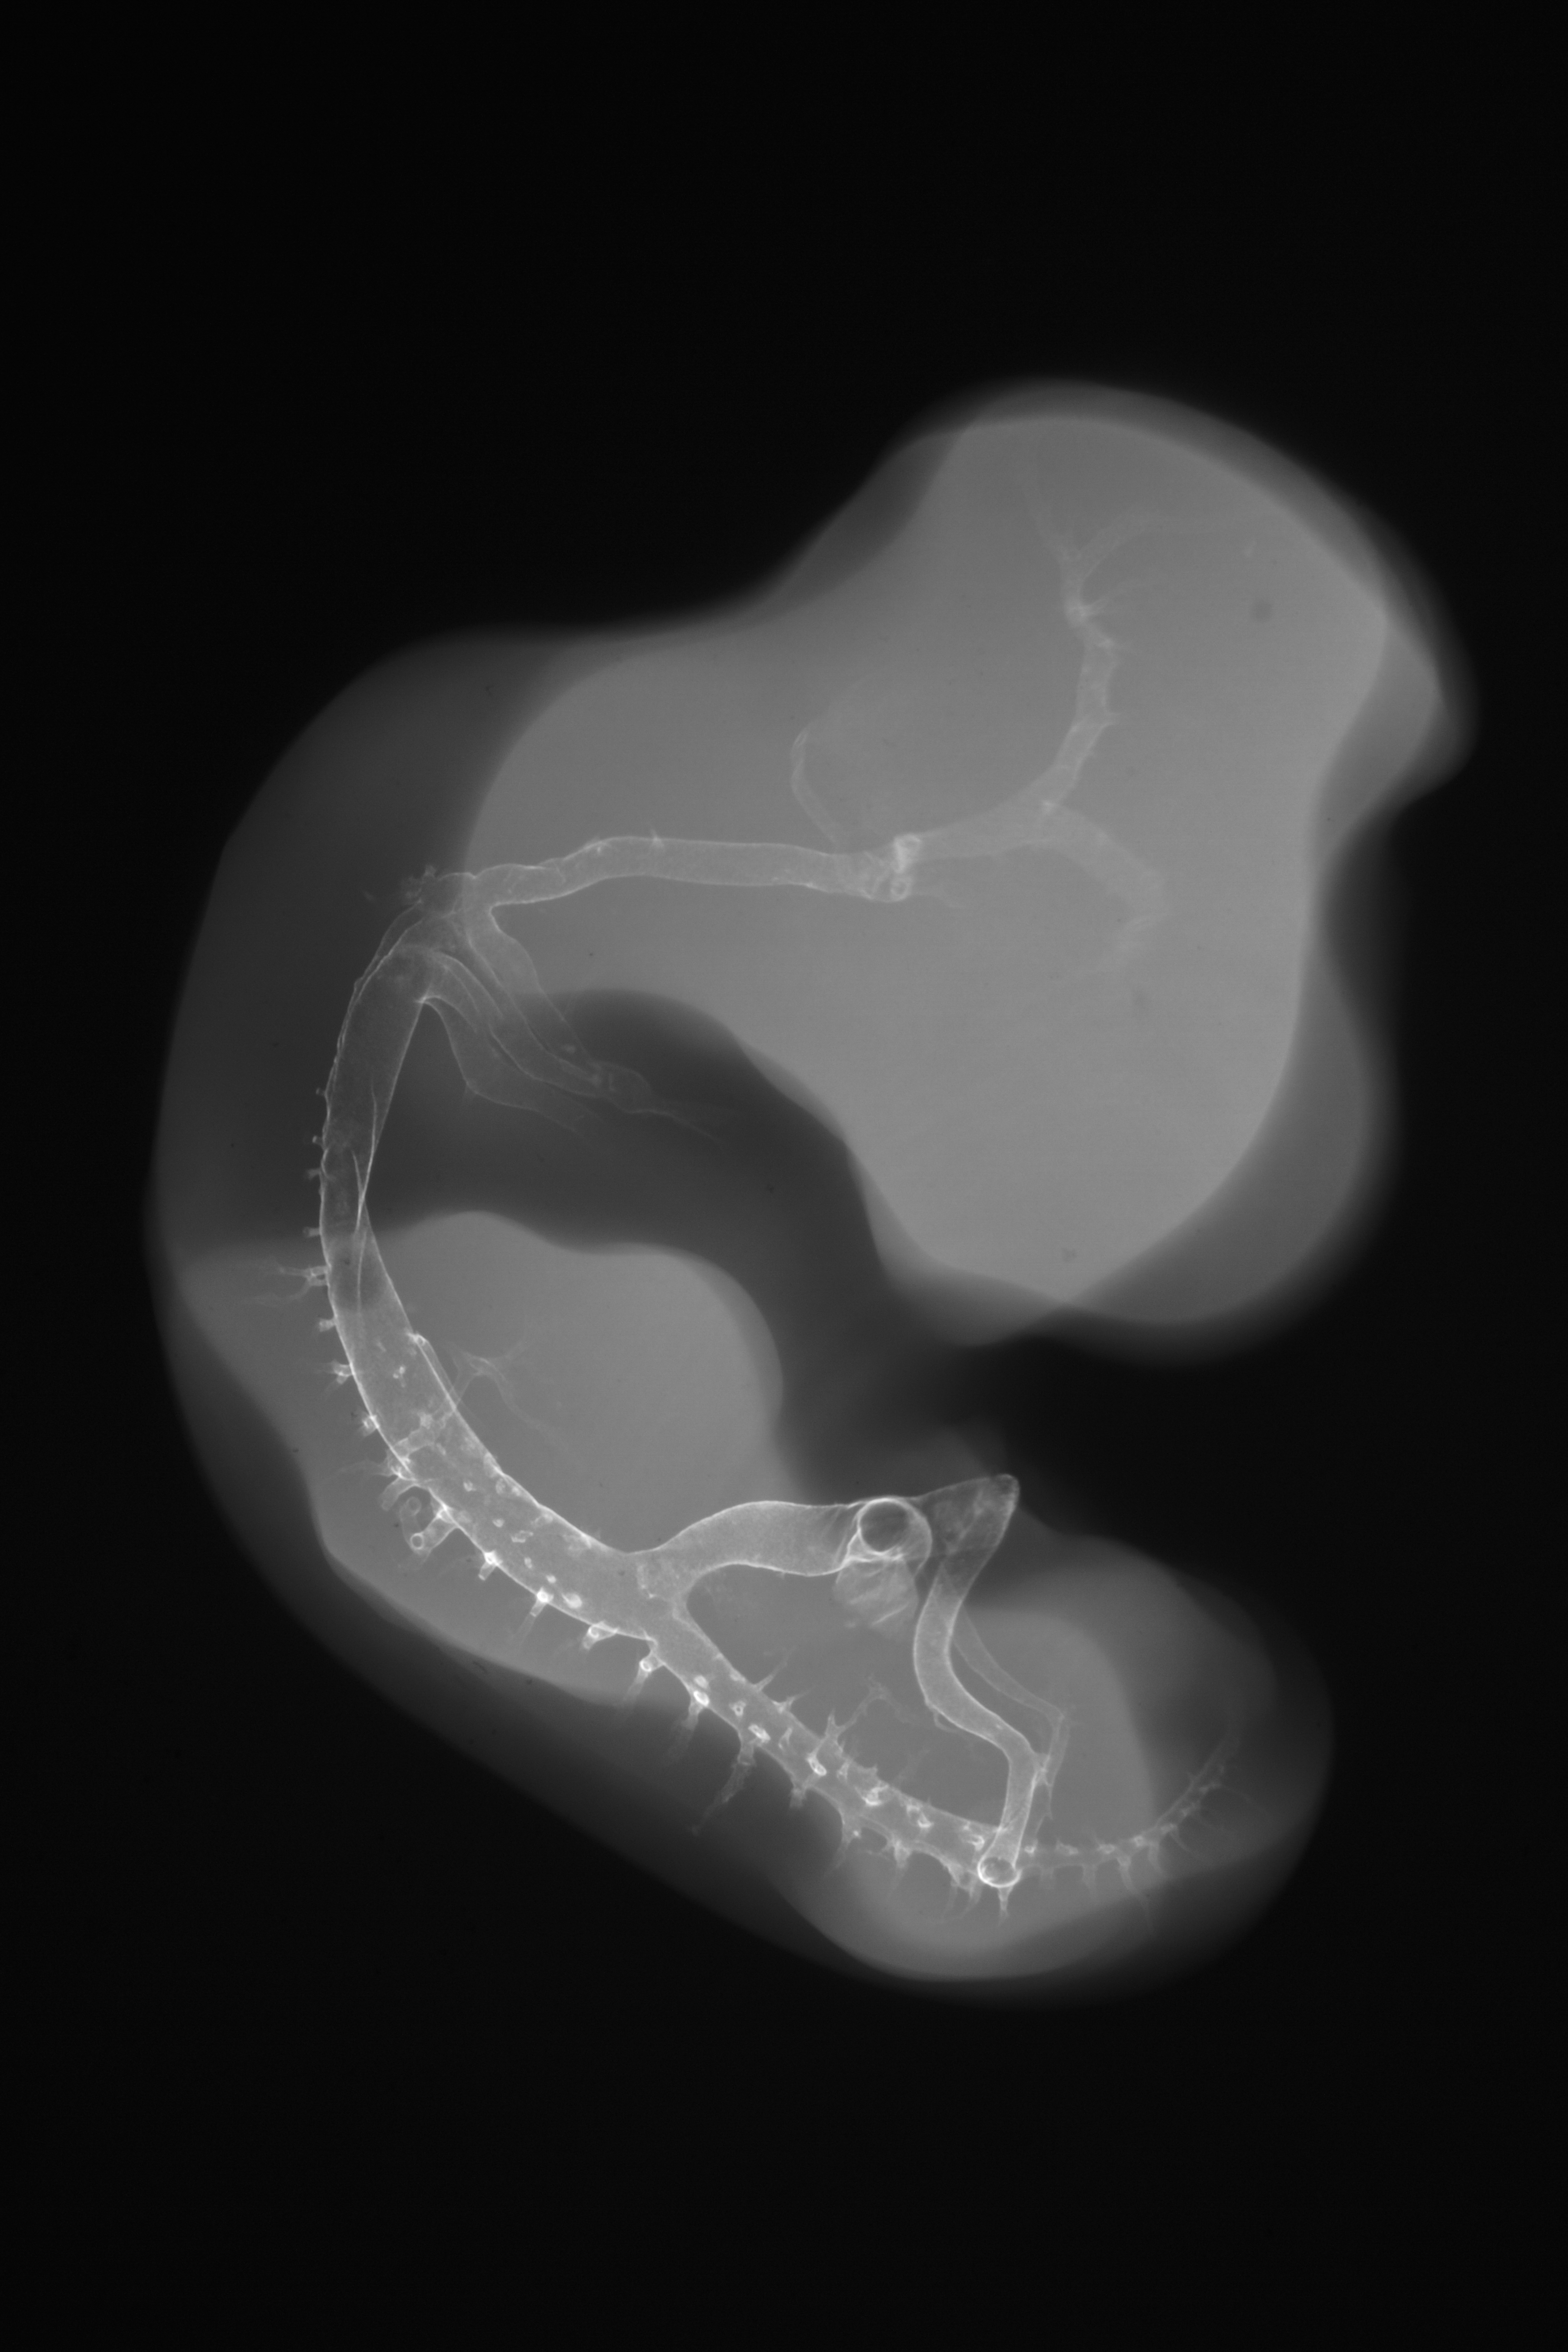

Hamburger-Hamilton (HH) Stage 26 (approx. 5 days)

X-Ray Micrographs